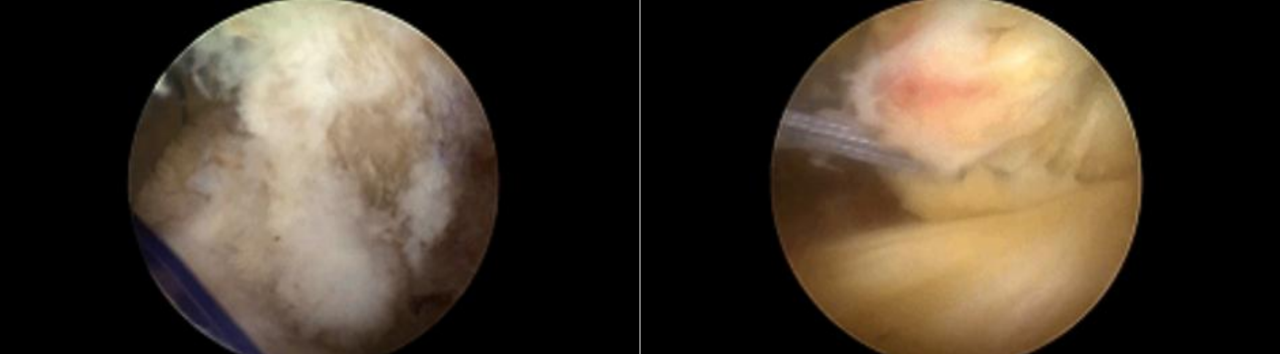

合并内侧半月板放射裂

撕脱骨折、内侧半月板放射裂

半月板骨道固定、双袢固定撕脱骨折